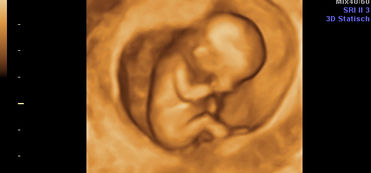

3D- und 4D- Ultraschall

Mit dem 3D- Ultraschall entstehen tolle Bilder von Ihrem Baby, die dann bei 4D von bewegt in Echtzeit sind.

Medizinisch hilft das 3D zB beim Auffinden von Lippenspalten oder Rückenmarksfehlbildungen.

In besonderem Maße macht es aber den werdenden Eltern eine riesige Freude, ihr Baby bildlich schon im Mutterleib sehen zu können. Wie es die Finger bewegt oder zB gerade den Mund öffnet.